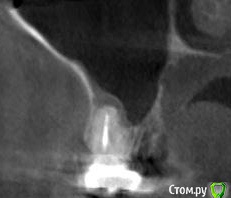

platerx Опубликовано 21 декабря, 2015 Поделиться Опубликовано 21 декабря, 2015 (изменено) Всем доброго времени суток.У меня есть пара вопросов: 1. Что можно сделать с зубом 2.7 История зуба такова:Зуб был сильно разрушен, но мне предложили попробовать пролечить его. Прочистили каналы, я некоторое время ходил с лекарством в зубе. Затем запломбировали каналы и поставили вкладку и коронку (консоль). Это было 2,5 года назад.С тех пор зуб меня иногда немного беспокоил, вызывая некоторый дискомфорт, но я не сильно обращал внимание. В последнее время он стал беспокоить сильнее: время от времени вызывает тянущие и распирающие ощущения, которые усиливаются при нажатии. Слегка побаливает десна и небо с внутренней стороны. Периодически ощущения пропадают. Прикладываю срезы КТ этого зуба. Что можно сделать с этим зубом ? Можно ли извлечь вкладку и перелечить каналы ? 2. При депульпировании зуба 2.4 врач не промывал каналы гипохлоритом (только хлоргексидином), после чего запломбировал их. Это нормально или стоит переделать? На зубе сейчас временная пломба, по прошествии 6 дней зуб не беспокоит. При постукивании есть небольшие неприятные ощущения. Изменено 21 декабря, 2015 пользователем platerx Ссылка на комментарий

DmitrySH Опубликовано 21 декабря, 2015 Поделиться Опубликовано 21 декабря, 2015 Добрый вечер.27. Есть очаг воспаления на одном из корней. Нужно снять коронку, оценить объём тканей. Если все ок, то извлечение вкладки и ревизия каналов.24. Сложно дать однозначный ответ. После выяснения ситуации с 27 планировать имплантацию в области 26 или 26, 27 (если с 27 все плохо) Ссылка на комментарий

St. Опубликовано 21 декабря, 2015 Поделиться Опубликовано 21 декабря, 2015 (изменено) Консоль не есть хорошо, тем боле на жевательных зубах. Это приводит к перегрузке.Кмк, на будущее стоит задуматься о смене конструкции в этой области. Изменено 21 декабря, 2015 пользователем St. Ссылка на комментарий